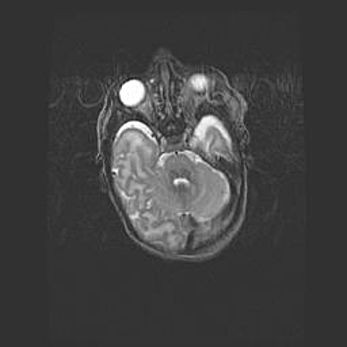

Аномалия Денди-Уокера. Признаки гипоплазии мозолистого тела.

Возраст: 5 месяцев 3 дня

Вес: 5550 г

Пол: мужской

Окружность головы: 39 см

Срок гестации: 40 недель

Аномалия Денди-Уокера – это порок развития головного мозга, для которого характерна триада симптомов: гипотрофия или аплазия червя мозжечка и/или полушарий мозжечка, расширение четвёртого желудочка с формированием ликворной кисты задней черепной ямки, гипертензионная гидроцефалия различной степени.

Гипоплазия мозолистого тела относится к дефектам внутриутробного этапа развития мозговой ткани, возникающим в процессе закладки структур головного мозга, что происходит на начальных этапах развития эмбриона.